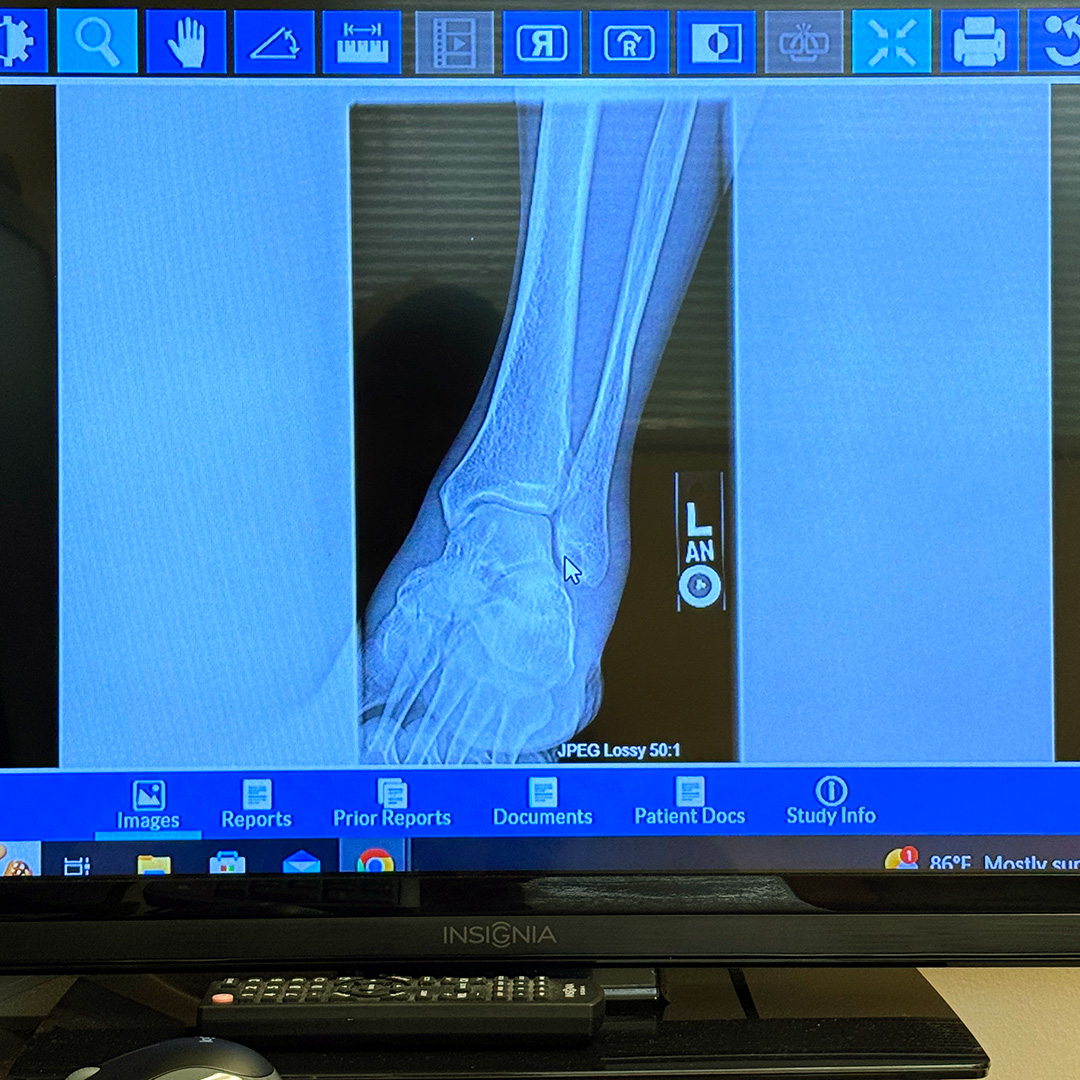

捻挫→剥離骨折→捻挫。

主治医の軽度ではあるけれど剥離骨折が見られるとの所見から、整形外科のアポイントを希望し出かけました。足を捻った経緯を説明し、先生が昨日撮影したX-Rayをくまなく診察していただきました。最後に様々な箇所を触診し出た結果は、【捻挫 | Sprain】でした!事故から二週間が経ち、相変わらず足首が腫れているので、いつもより大きく捻ってしまったのかもしれません。結果としては良かったのですが、お騒がせいたしました。